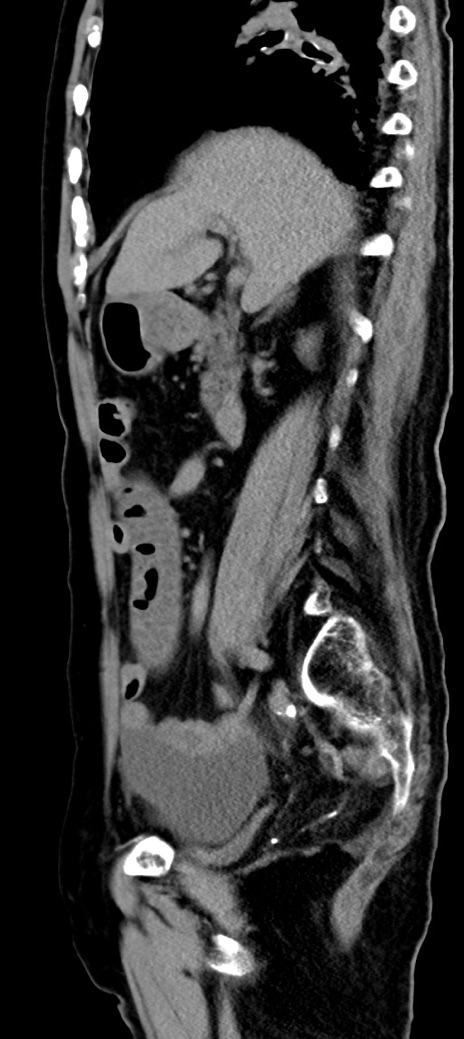

横断像

冠状断像